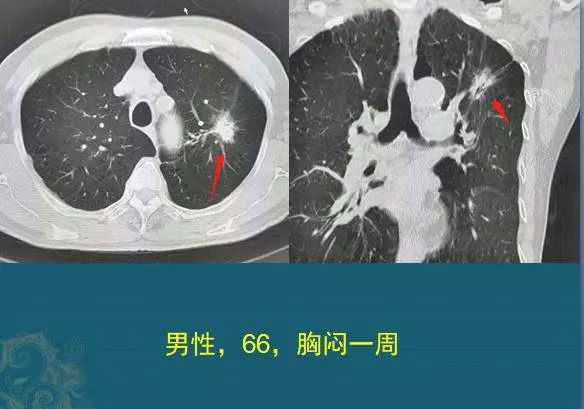

下图也是一位66岁男病人,胸闷体检,发现肺腺癌,右图肺结节内部可见黑色小条形支气管征。

1582983034796_f2cdd04caa7851ed5369eb4eaa643c89.jpg